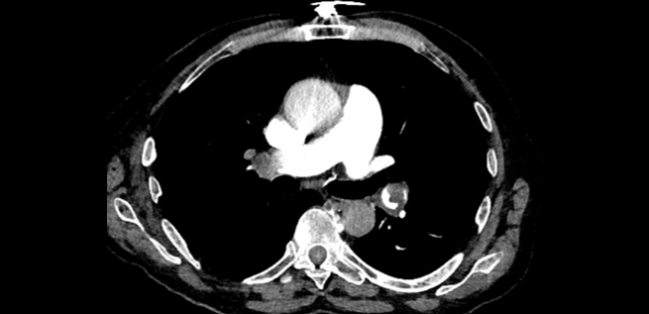

Photo Credit: Jay Giri